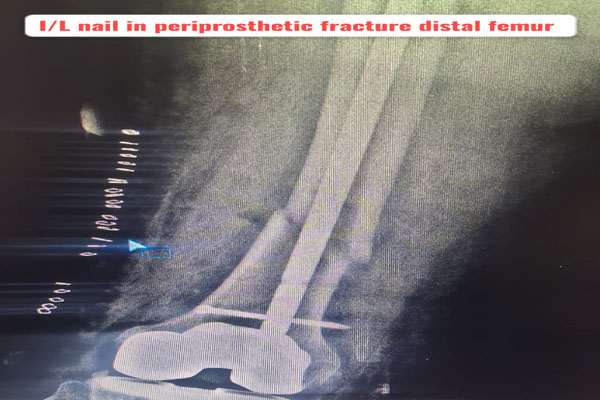

Fracture of bones is commonly handled by almost all orthopaedic surgeons in India. But dealing with comminuted intra-articular fractures (involving joints) is a night mare for most of them. It requires special expertise and experience to deal with such kind fractures. It can involve pelvic acetabular fracture, upper portion of thigh bone ( hip), lower portion of thigh bone ( femur), upper portion of arm bone (humerus head), lower portion of arm bone (humerus), lower portion of forarm bone (lower end of radius) fracture of heel bone, etc. The idea is to maintain the joint (articular) integrity and prevent the permanent loss of movements at that joint. It requires image intensifier (c-arm) to do these surgeries. May be artificial bone or autograft (patient’s own bone taken from iliac bone) to fill in the bone defect/ loss if present. The fracture may take 2- 3 months to heal. Patient may require prolonged physiotherapy to gain near normal range of motion exercises.